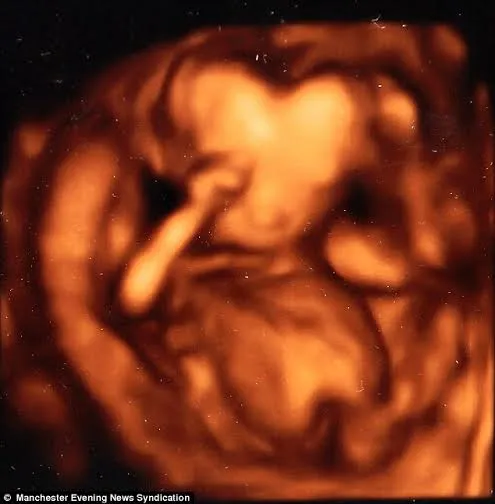

Cậu bé có đầu hình trái tim khi siêu âm 3D

(PLO) - Một người mẹ đã bị sốc khi thấy hình ảnh siêu âm lúc 16 tuần tuổi của con mình với cái đầu hình trái tim.

Chị Beverley Winter (20 tuổi, đến từ Stockport, Anh) không thể tin nổi khi hình ảnh siêu âm 3D cho thấy con trai chị có hình dạng đầu kì quặc. Cả hai vợ chồng đều rất lo lắng vì năm trước chị Winter đã bị sẩy thai.

Cái đầu của cậu bé lúc 16 tuần tuổi có hình trái tim khi siêu âm 3D

Tuy nhiên, các bác sĩ cam kết rằng đầu của bé vẫn còn phát triển. 5 tháng sau, vào ngày 8-9 năm nay chị đã sinh được một cậu con trai với cái đầu rất bình thường. Cậu bé tên là Logan Platt. Nhiều người cho rằng hình ảnh trên là do góc siêu âm và nước ối đã che lấp một phần đầu.